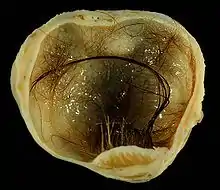

| A small (4 cm) dermoid cyst of an ovary, discovered during a C-section | |

A dermoid cyst is a teratoma of a cystic nature that contains an array of developmentally mature, solid tissues. It frequently consists of skin, hair follicles, and sweat glands, while other commonly found components include clumps of long hair, pockets of sebum, blood, fat, bone, nail, teeth, eyes, cartilage, and thyroid tissue.

While all ovarian cysts can range in size from very small to quite large, dermoid cysts are not classified as functional cysts. Dermoid cysts originate from pluripotent germ cells (which are present at birth) that differentiate abnormally, developing characteristics of mature dermal cells. Complications exist, such as torsion (twisting), rupture, and infection, although their incidence is rare. Dermoid ovarian cysts which are larger present complications which might require removal by either laparoscopy or laparotomy (traditional surgery).[3][4] Rarely, a dermoid cyst can develop in the vagina.[5][6][7]